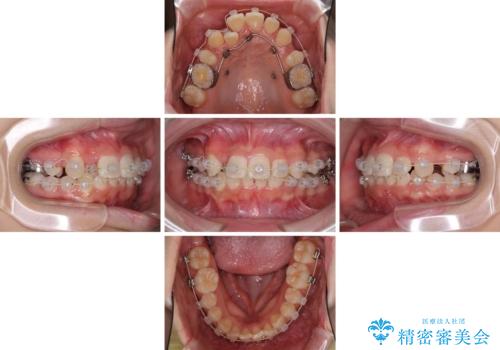

- 八重歯やデコボコをインビザラインで治療したいとのことで来院された患者様です。

インビザライン単体で治療を行うには叢生が強いと判断されたため、事前にワイヤー装置で抜歯矯正を行い、ある程度改善してからインビザラインにて仕上げていくこととしました。